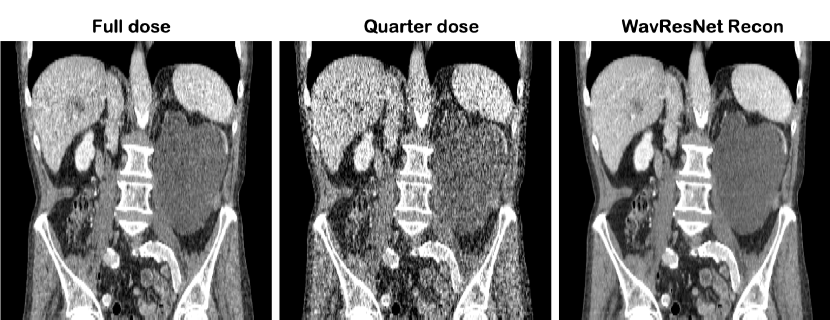

VI-A Categories of the existing approaches

This section starts with reviews of various network architectures and design principles for image reconstruction problems. Fig. 7 illustrates typical architectures at a high level, which are commonly used in the literature. However, this field is rapidly growing, so a complete review of the design principles is beyond the scope of the paper.

VI-A1 Image-domain learning

In image domain approaches [165, 180, 157, 181, 162, 167, 163, 158, 161], artifact-corrupted images are first generated from the measurement data using some analytic methods (e.g., FBP, Fourier transform, etc.), from which neural networks are trained to learn the artifacts (see Fig. 7(a)). For example, the low-dose and sparse CT neural networks [157, 181, 162, 163, 158, 161] belong to this class, where the noise corrupted images are first generated from the noisy or sparse view sinogram data using FBP, after which the artifacts are learned by comparing with the noiseless label images. In MR applications, the early U-Net architectures for compressed sensing MRI [182, 167] were also designed to remove the aliasing artifacts after obtaining the Fourier inversion image from the downsampled k-space data.

In particular, FBPConvNet [162] showed that image domain networks can be derived by unrolling sparse recovery for one specific class of inverse problems: those where the normal operator associated with the forward model is a convolution. For this class of inverse problems, a CNN then emerges. This class of normal operators includes MRI, parallel-beam X-ray CT, and diffraction tomography (DT).